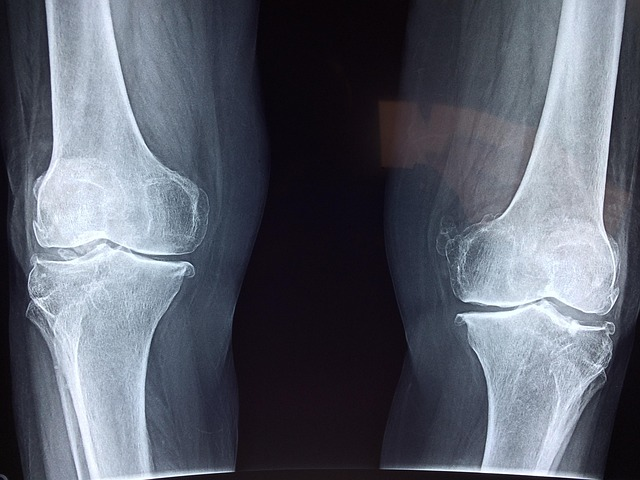

현대 사회에서 관절 통증은 더 이상 노년층의 전유물이 아닙니다. 장시간 앉아서 일하는 직장인, 격한 운동을 즐기는 20~30대, 그리고 무릎 사용량이 많은 40~50대까지 누구나 관절 건강에 신경 써야 하는 시대입니다. 특히 무릎, 손목, 어깨 관절은 일상생활에서 가장 많이 사용하는 부위로, 사용 빈도가 높아질수록 마모되기 쉽습니다.

하지만 관절 통증은 초기에는 단순한 피로감으로 느껴질 수 있어 많은 이들이 치료 시기를 놓치고 맙니다. 이때 가장 효과적인 관리법 중 하나가 바로 관절 영양제 추천 제품을 활용한 예방적 복용입니다.